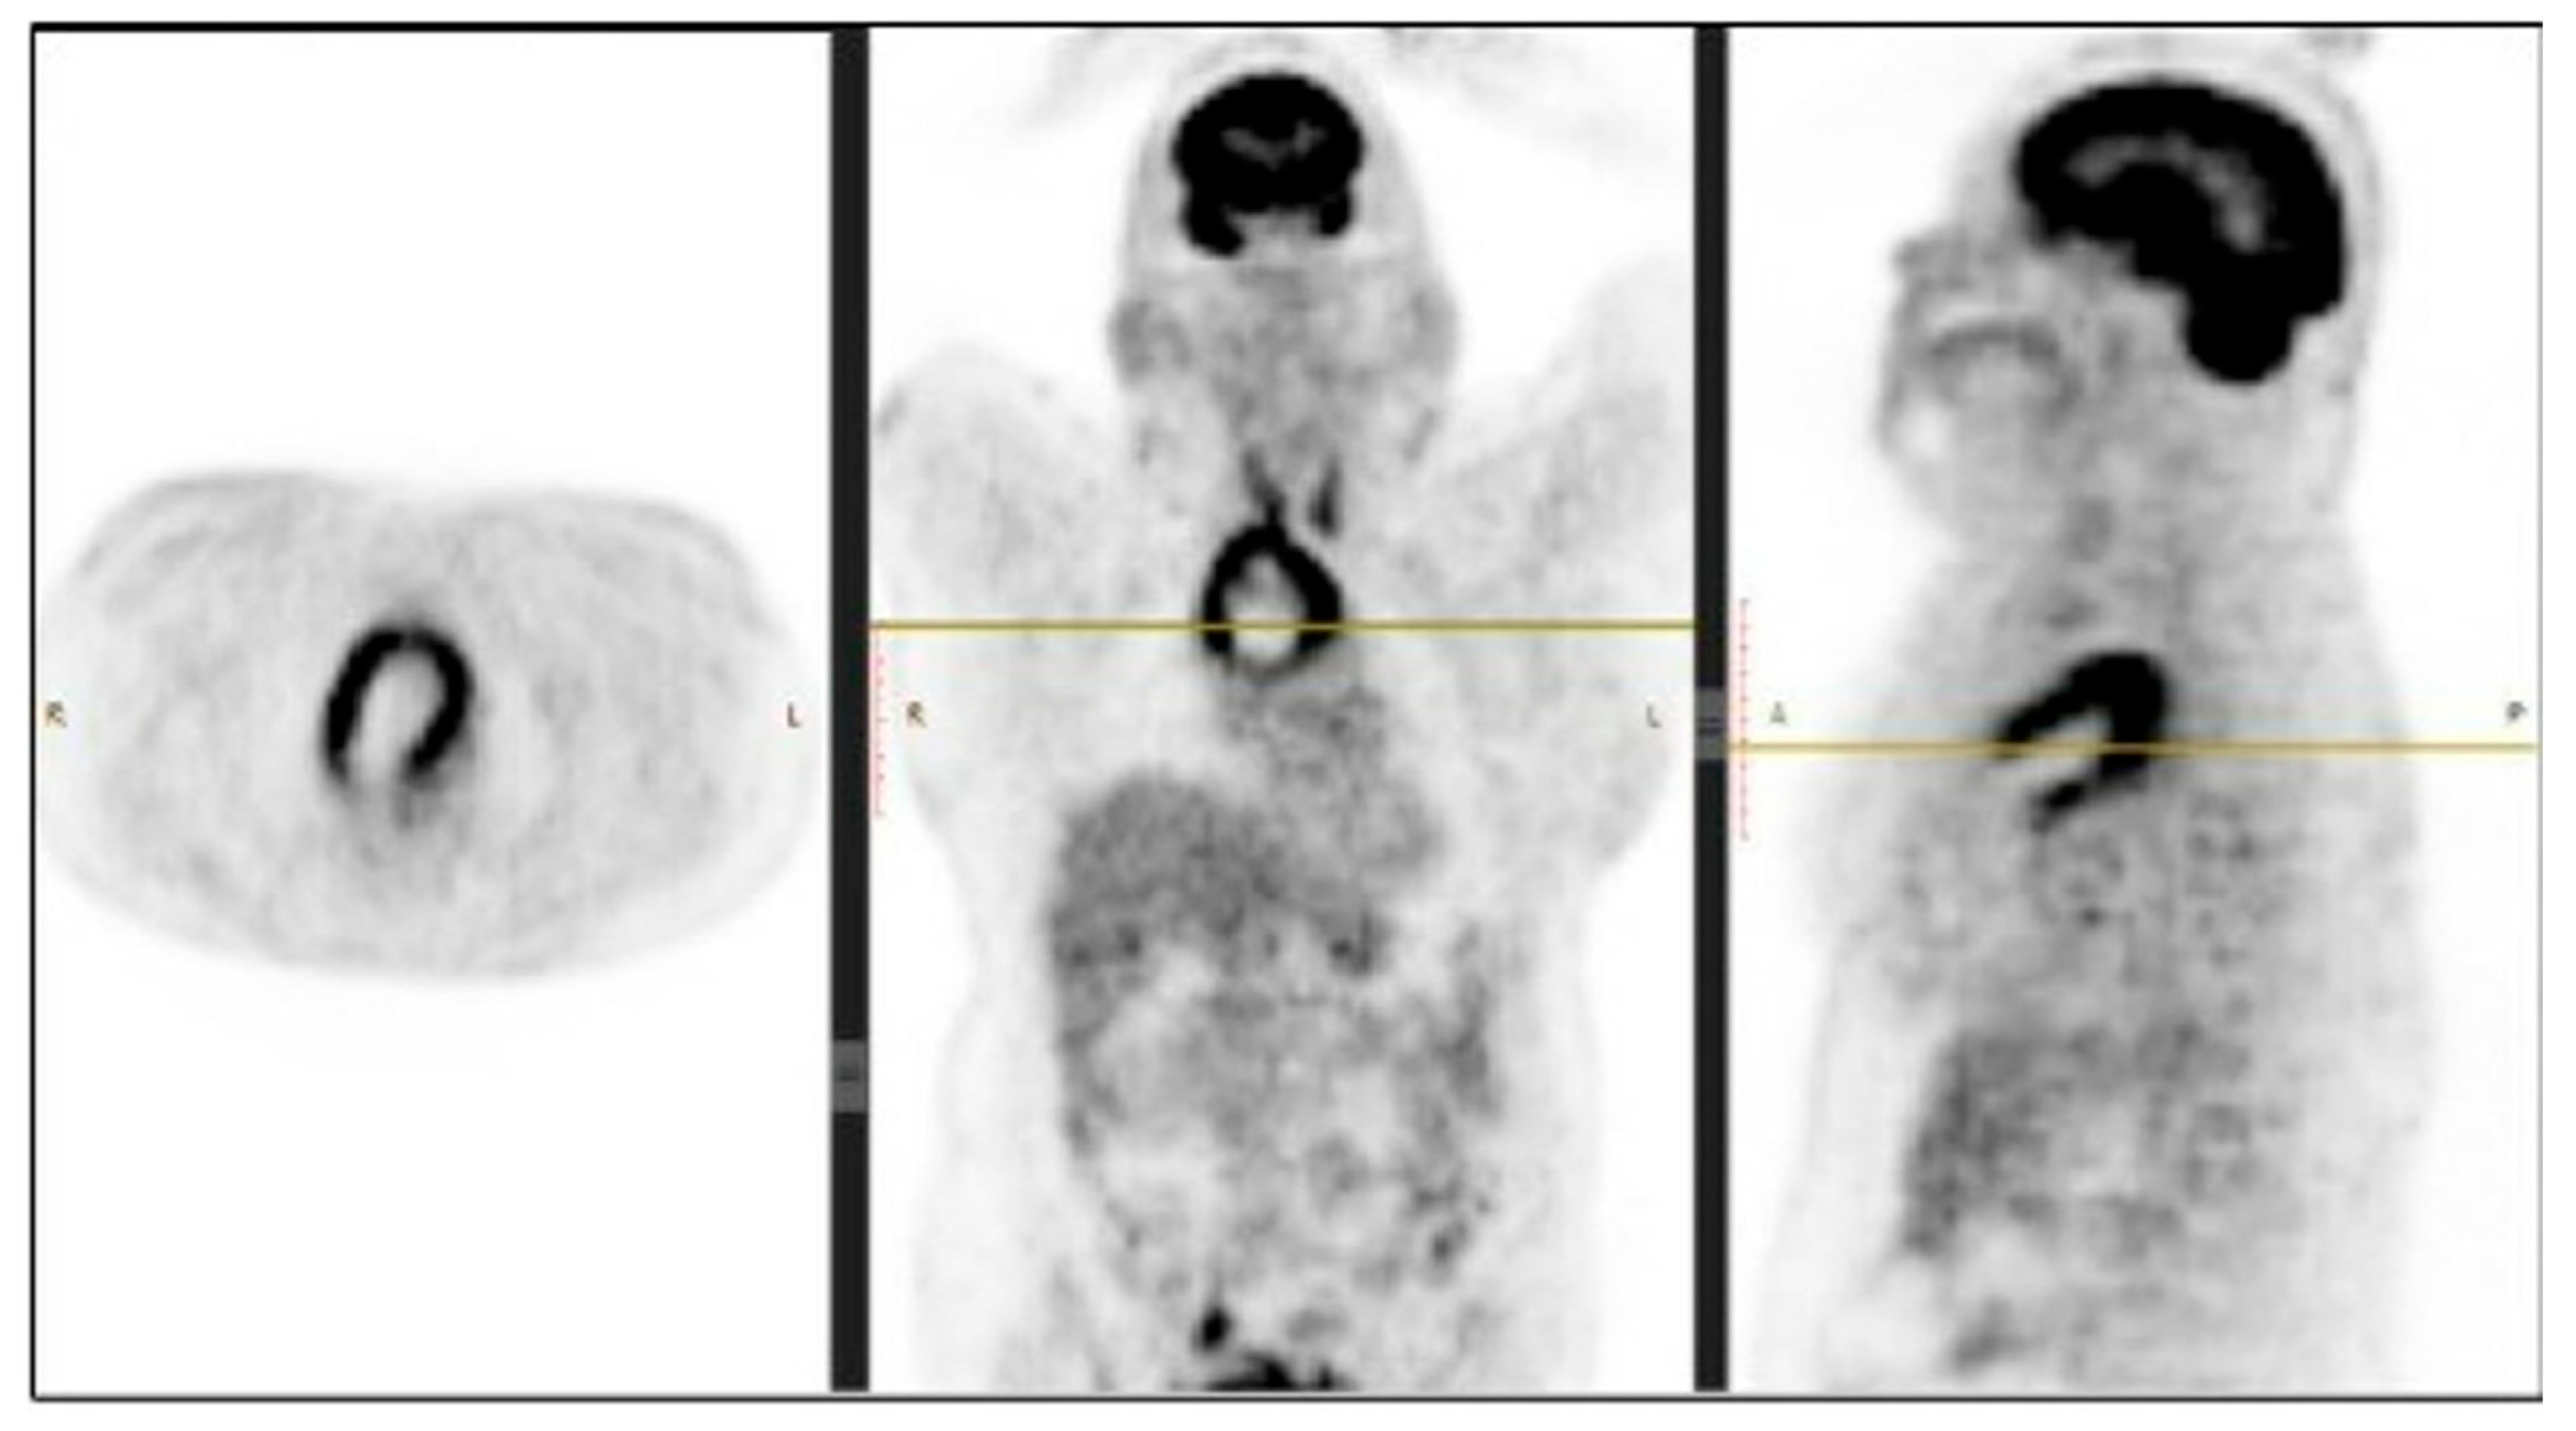

The performed contrast-enhanced computerised tomography (CECT) of the chest revealed a large, well-defined, centrally necrotic, peripherally enhancing mass lesion in the superior mediastinum extending to the anterior mediastinum. There was displacement of the trachea to the left side, compression of brachiocephalic veins and proximal SVC, and a possibility of sclerotic skeletal metastasis in the vertebrae (Figure 2). A CT-guided biopsy was planned, and a fluorodeoxyglucose (FDG) positron emission tomography (PET) scan (SUV-13.1) was performed to differentiate between a malignancy or a mass with an infective lesion and to look for metastasis. The scan revealed a large 10.7 × 6.5 × 6.2 cm well-defined mass lesion of neoplastic aetiology with a mass effect—likely of thymic origin, but with no evidence of metastasis (Figure 3).

Figure 3. PET scan showing metabolic activity in the mediastinal mass. Abbreviations: R: Right; L: Left.